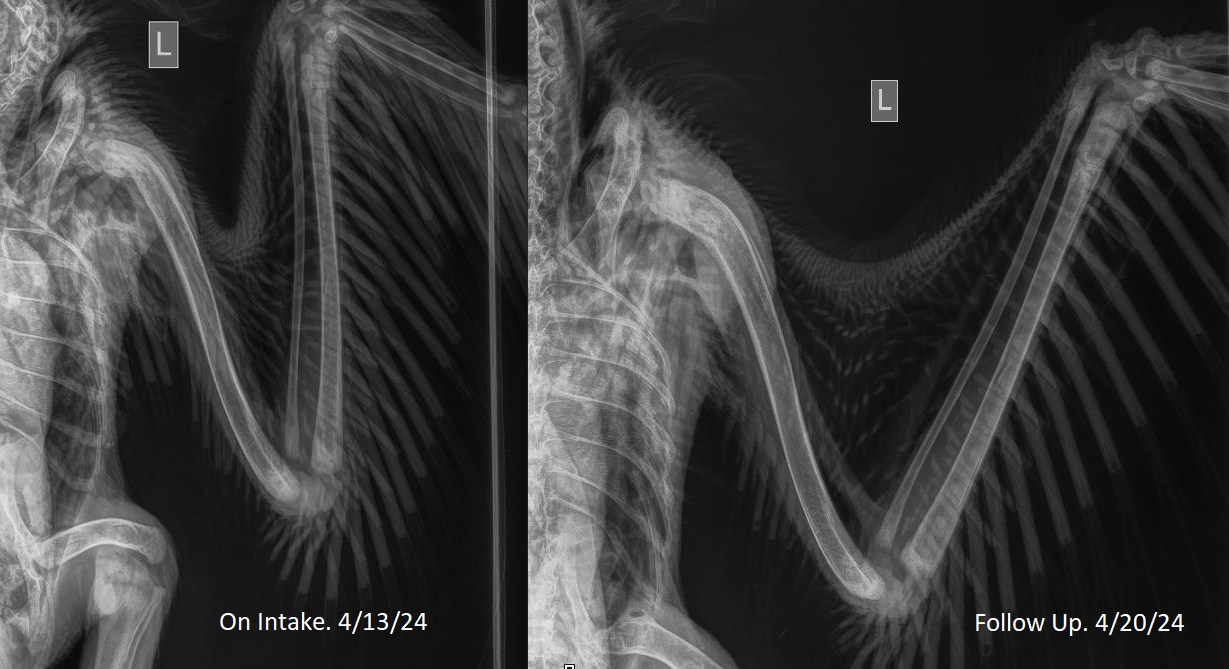

2024年4月中旬,一隻編號為24-159的受傷小鷹在伊利諾伊州被發現。保護區在臉書(

Facebook)上發文解釋說,24-159號小鷹的巢掉在了一片灌木叢中,它的左尺骨、肱骨和

冠狀骨(肩部的骨頭之一)骨折。由於它多處受傷,將其送回巢穴不是辦法,因此他們決

定將其安置在墨菲的籠子裡。

編號為24-159的小鷹的翅膀骨折。(世界鳥類保護區提供)